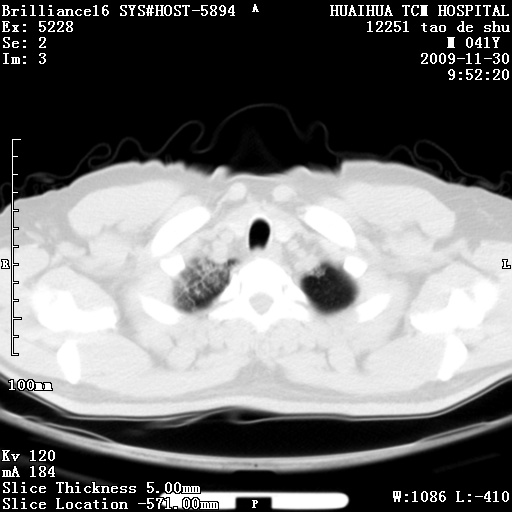

男性,41岁,林业局干部。5天前(2009-11-25)因受寒咳嗽发热在市一医院门诊就诊,胸片报告支管炎。门诊治疗无好转,遂转入我院住院治疗。现主要为发热,38度,咳嗽较轻。血象不高,中性72%,嗜酸性细胞未见报告。血小板8万。尿有蛋白管型。肝功能异常。心电图:阵发性心动过速。请分析ct是什么病。

补充图片:

考虑非肺染 肝脏多发性小囊肿

考虑间质性肺炎。肝脏多发性小囊肿

iip,肝脏多发性小囊肿